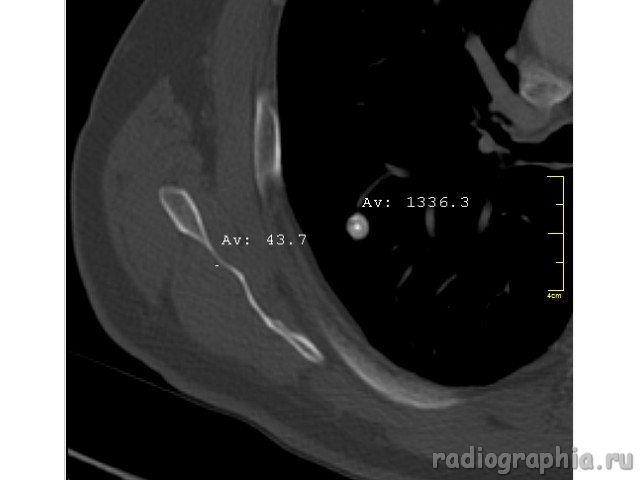

Одиночный узел правого лёгкого.

На рутинном снимке ОГК, был выявлен одиночный узел; по протоколу выполнили КТ. Какое было бы ваше заключение; и как бы Вы поступили если у вас нет возможности выполнять КТ?